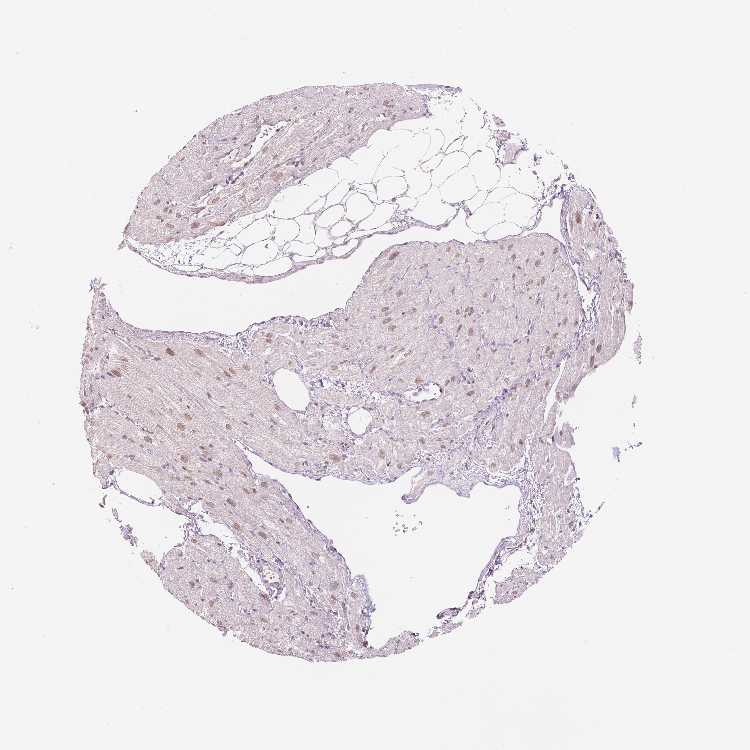

HEART MUSCLE - Antibody stainingi

Antibody staining in the annotated cell types in the current human tissue is reported as not detected, low, medium, or high, based on conventional immunohistochemistry profiling in selected tissues. This score is based on the combination of the staining intensity and fraction of stained cells.

Each image is clickable and will lead to virtual microscopy that enables deeper exploration of all samples and also displays staining intensity scores, fraction scores and subcellular localization as well as patient and tissue information for each sample.

Antibody HPA027179Antibody CAB068193

Cardiomyocytes MediumLow